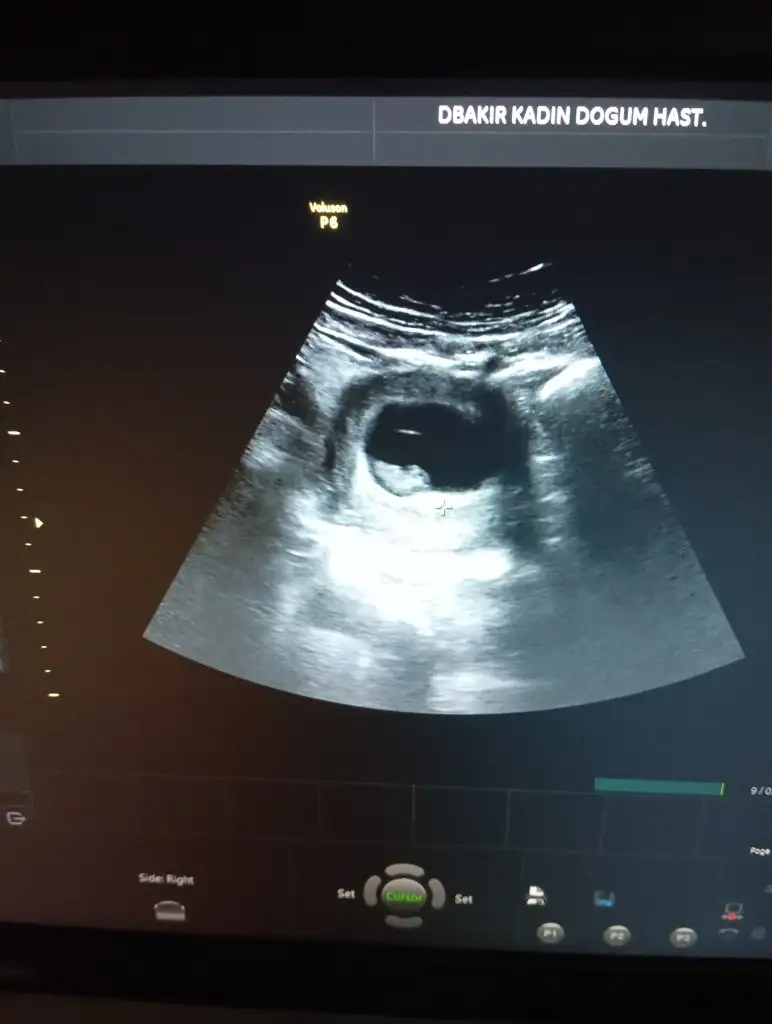

Bana da tahmin de bulunur musunuz 9 haftalıgiz

kız olabilir kese yuvarlak